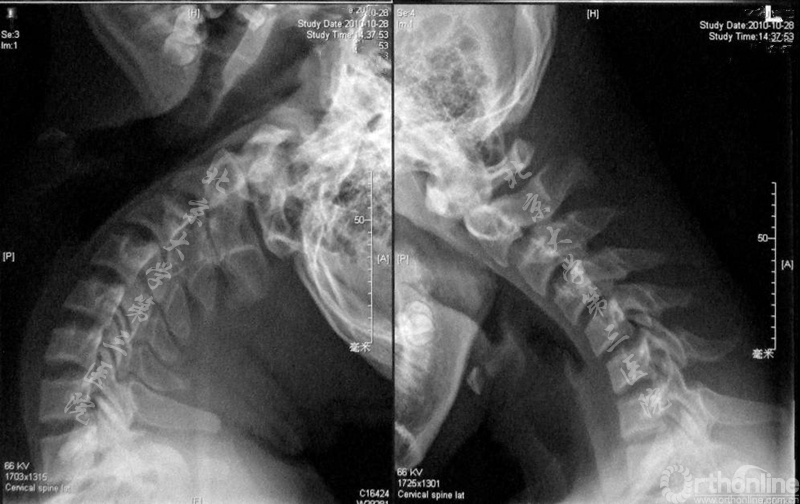

平山病患者的影像学特点为颈部屈伸活动明显增大(图2),中立位核磁脊髓无明显受压,但屈颈位MRI可见下段颈髓前移,颈脊髓在屈颈位时受到挤压(图3)。

图2.过伸过屈位X线